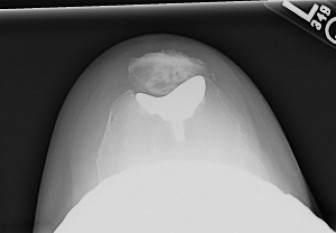

Patellofemoral Arthroplasty: Avoid Failure, End Patellofemoral Pain

A 48-year-old female patient presents with anterior left knee pain. She has had a history of recurrent patell…